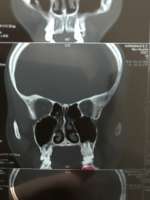

IMG201708272317[...].jpg (386Кб, 1944x1840)

Искривление носовой перегородки третьей степени, лол. Нос смещен влево. Одна ноздры не дышит. Всрато и ваще пиздец.

А у многих тут збс носы, хз, чего вы паритесь.